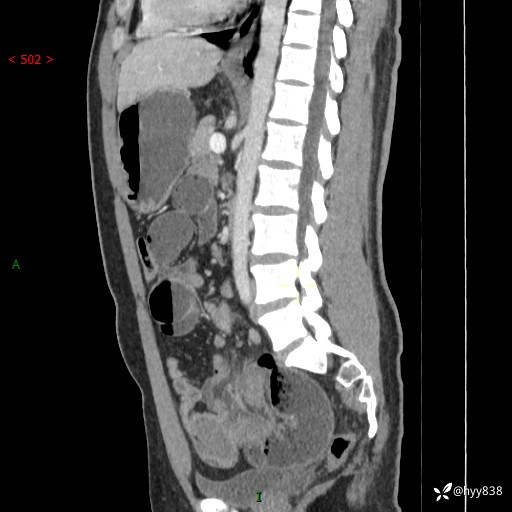

年轻男性,腹痛5月余。除了肠梗阻,你还能看到什么---结果公布~

主诉:腹痛5月余。

现病史:患者于5月前无明显诱因开始出现腹痛,上明显,为间断性胀痛不适,无畏寒发热,无心慌气促等特殊不适,遂来我院。我院门诊遂以“腹痛原因待查”收入我科。 起病以来,患者精神、饮食、睡眠欠佳,大小便正常。体力体重无明显变化。

腹部CT增强扫描(动脉期+静脉期)